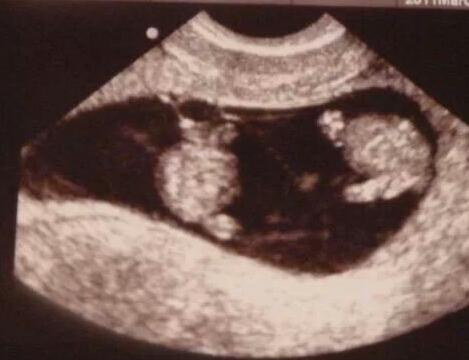

Ok neither of these are very good images, but here is the 7 week u/s:

image

and here is the 10 week one:

From my mosts recent u/s, I only have photos of the individual babies and I don't have them on my phone right now, but I can upload tomorrow if that helps.

Definitely di/di. There's really no mistaking that in my opinion. These are my mo/di at 10 weeks. Can barely seem a dividing membrane.

• I agree with @Mrs. Alice. My mo/di's looked like the picture she posted. Their membrane has always been very thin.

• Yep same here....there was no visible membrane at all on my first u/s (lucky me for not knowing enough to worry). I would say yours are clearly di/di.

• Looks like mine. Definitely didi!!